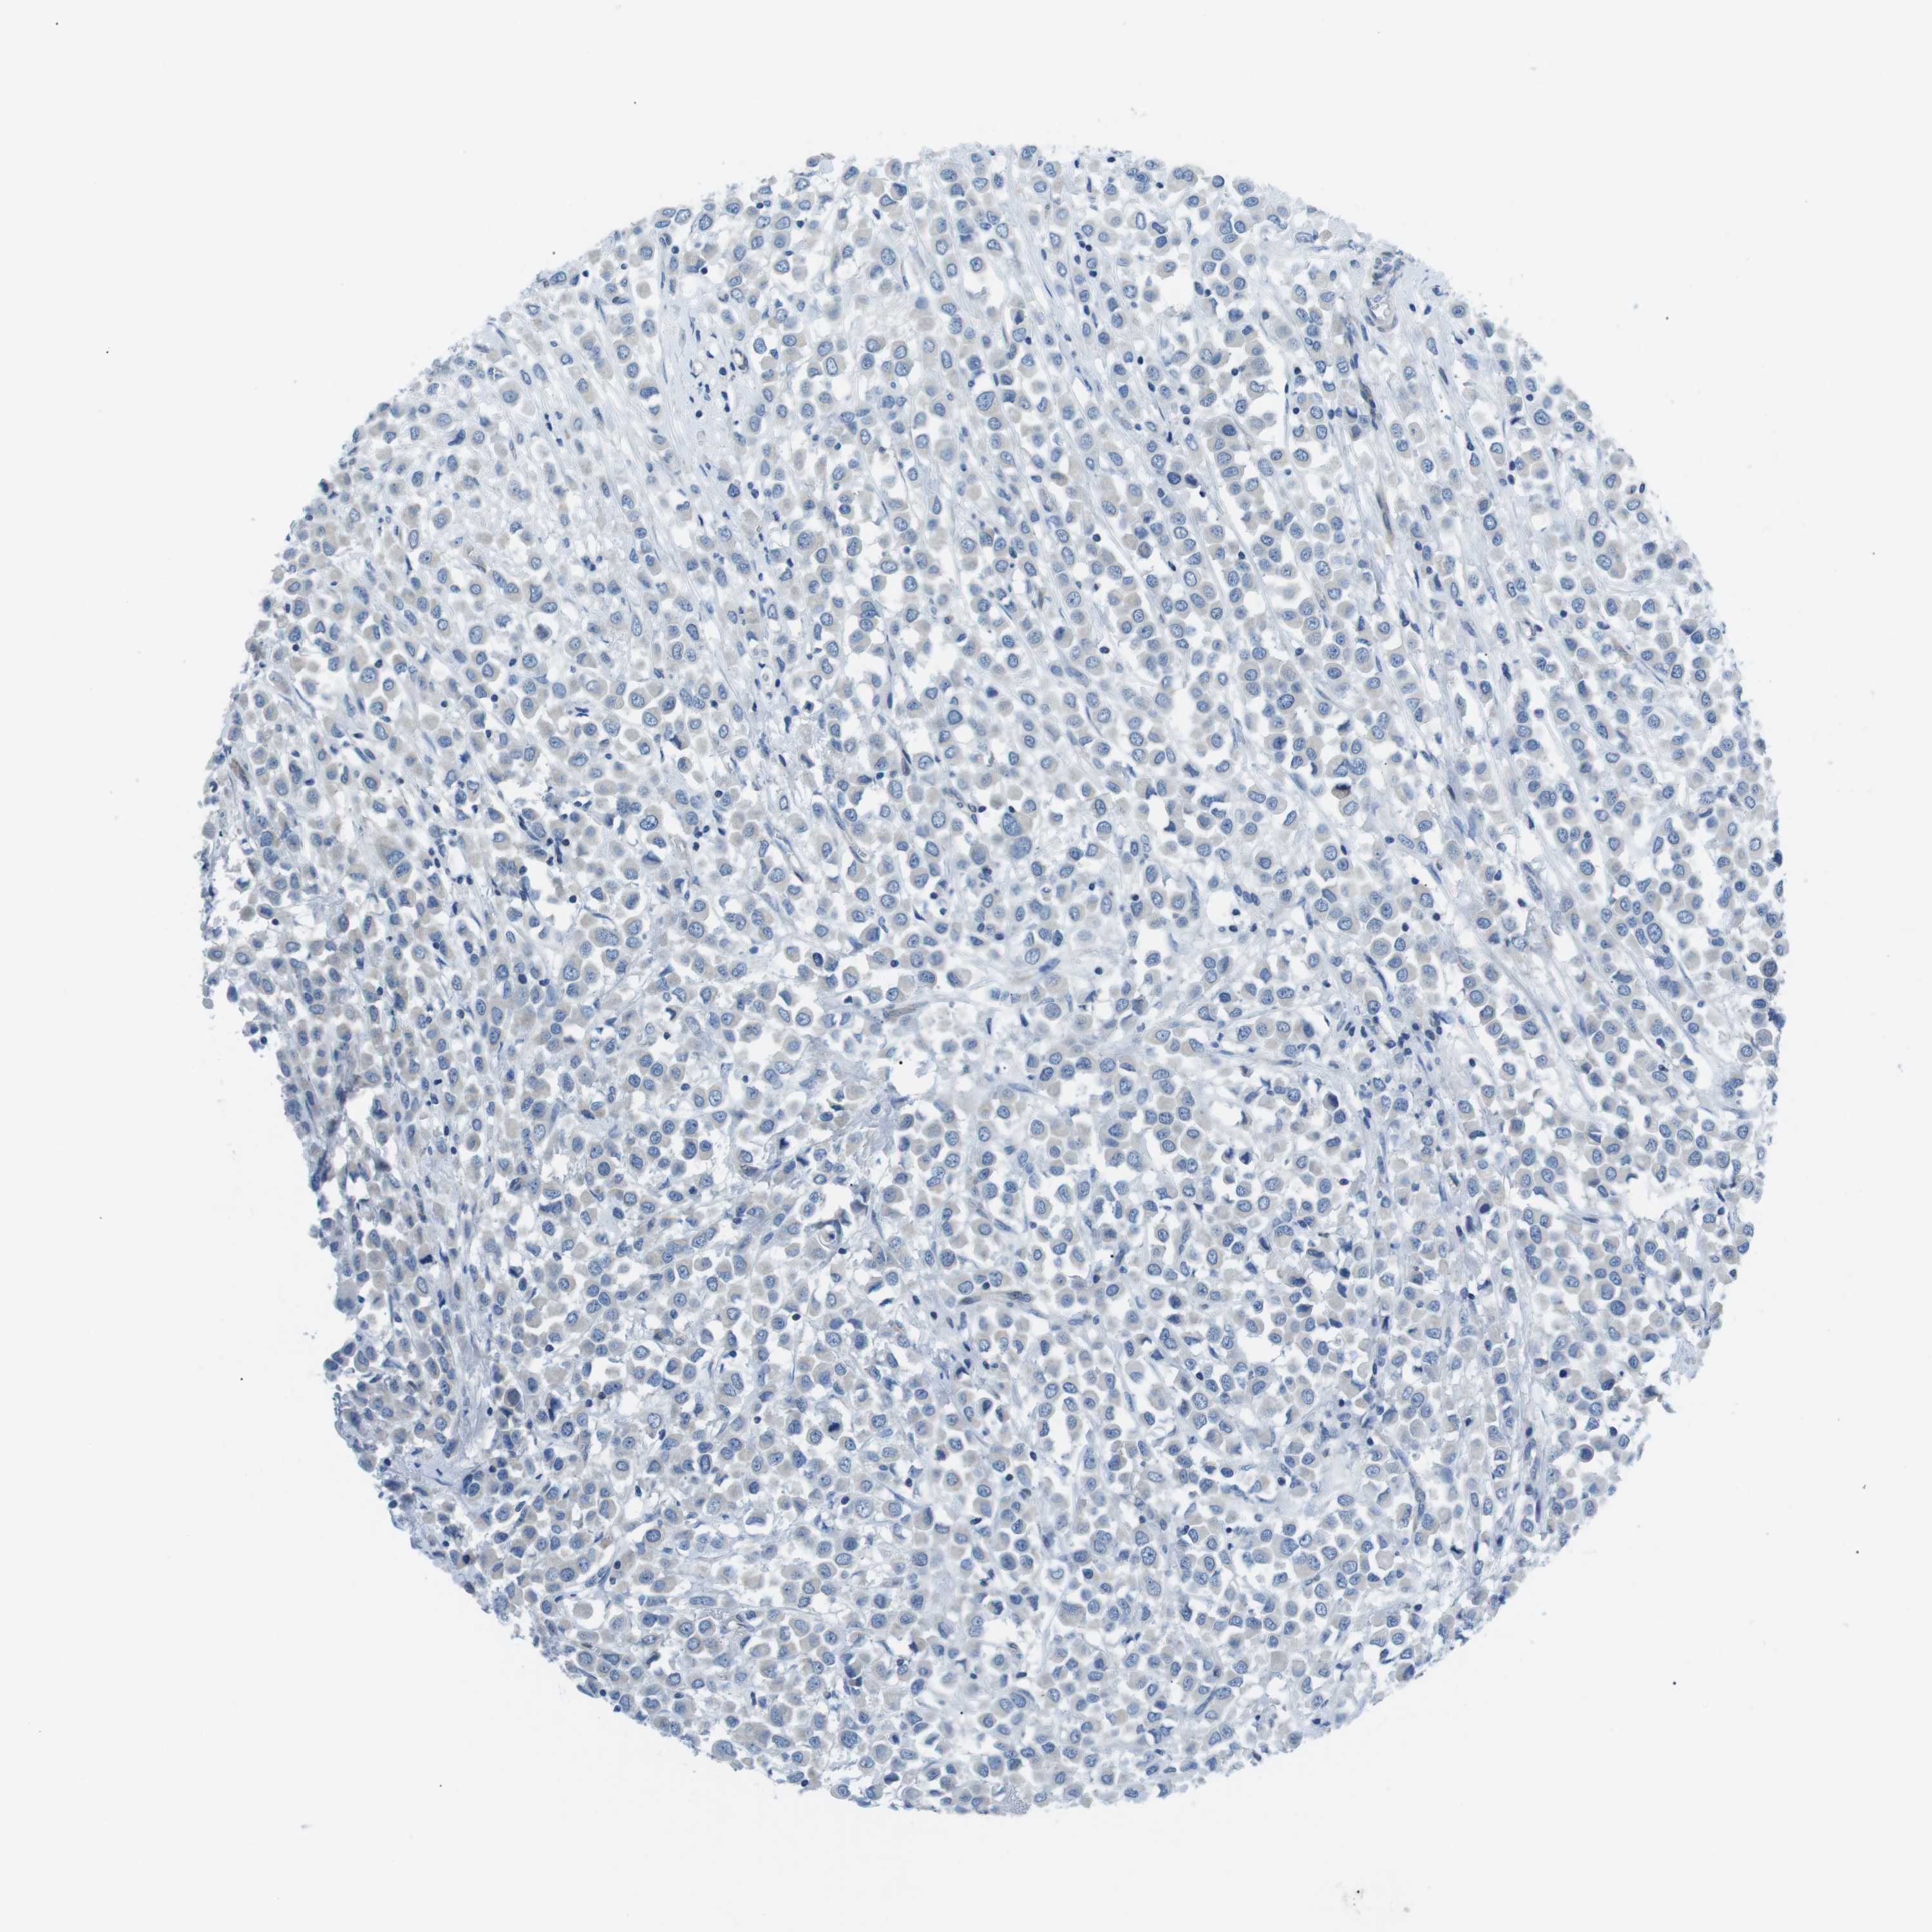

CANCER BREAST CANCER Show tissue menu

BRCA TCGA BRCA VALIDATION PROTEIN EXPRESSION